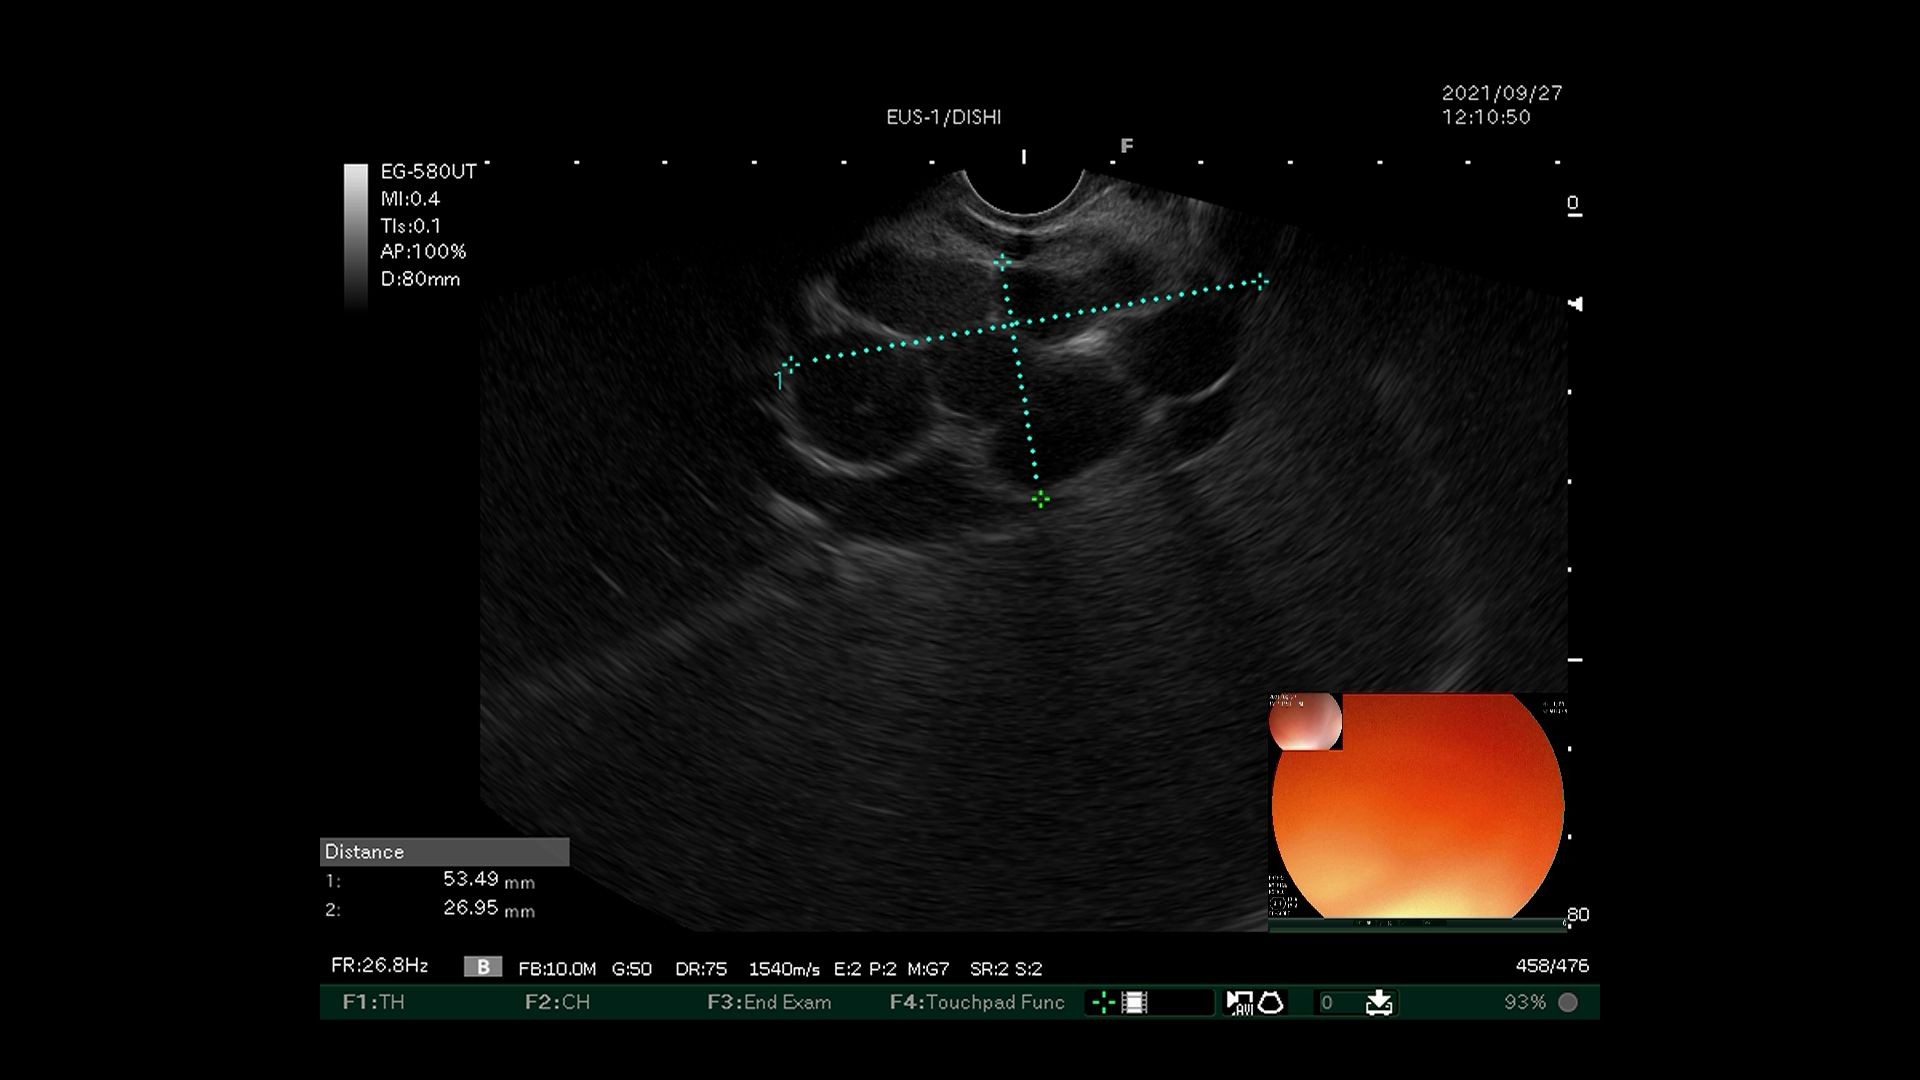

2)超声内镜探查食管下段近贲门处,发现曲张静脉并测量直径。

超声内镜引导下弹簧圈置入联合组织胶栓塞术先使用超声内镜识别胃底曲张静脉,选取曲张静脉内径最宽处,在超声内镜引导下经食管下段、膈肌角以19G穿刺针穿入曲张静脉,置入数枚略大于曲张静脉内径的弹簧圈,然后用“高糖-组织胶-高糖”三明治法于曲张静脉内注射组织胶,最后使用超声内镜确认曲张静脉血流信号消失。该技术可明显降低异位栓塞的风险,但需要手术者同时具有超声内镜及静脉曲张两个亚专业的熟练操作技巧,手术大出血风险极高,若有不慎即可导致术中患者死亡。